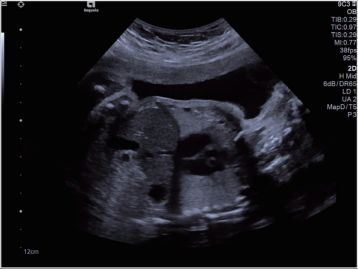

超聲圖像舉例

原理:超聲的原理是用超聲波穿透人體,當(dāng)聲波遇到人體組織時會產(chǎn)生反射波,通過計算反射波成像;

應(yīng)用:主要用于腹部、婦科、心臟等的檢查;

優(yōu)點:多方向觀察,實時成像;

缺點:超聲受氣體干擾大,對于腸道等含氣體較多的器官,超聲診斷準(zhǔn)確率會降低,所以一般腸道檢查使用腸鏡;